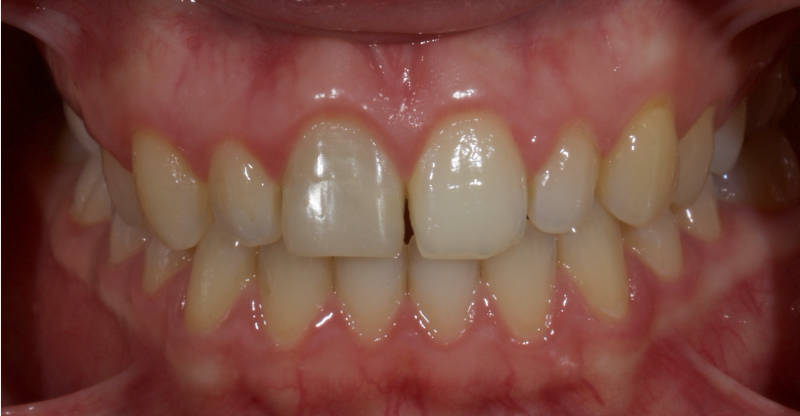

This article explores a more modern, minimally invasive approach to discolored non-vital teeth using the “modified walking bleach” approach. Figure 3 (before treatment) and Figure 4 (after treatment) show an example of this highly conservative approach.